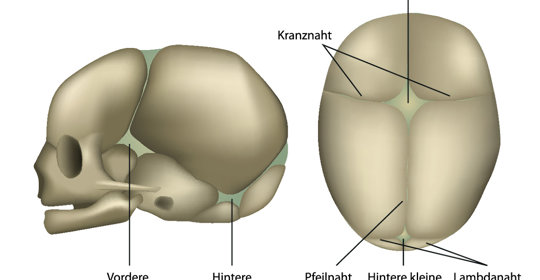

嬰兒囟門:頭痛、噁心、前囟膨脹